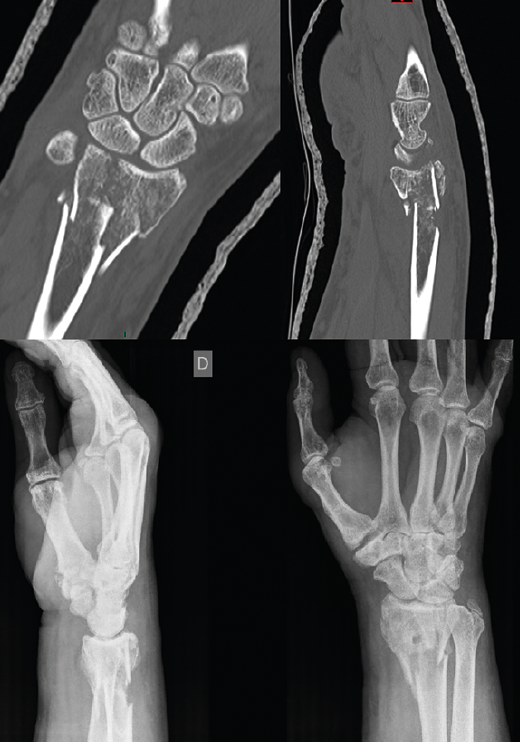

Figura 3. Ausencia de consolidación establecida, 6 meses de la fractura.

A los 6 meses no existió progreso radiológico y la falta de consolidación se manifestó claramente con pérdida de la reducción progresiva y dolor (Figura 3). En ese momento, se realizó la segunda cirugía abierta: extracción del material de síntesis que presentaba tornillos distales rotos (los bloqueados) y aflojados el resto, toma de muestras para cultivo, toma de muestra para anatomía patológica, limpieza del foco, perforación del hueso distal y proximal, colocación de autoinjerto tricortical estructural impactado y esponjosa de la cresta ilíaca y nueva síntesis con placa Acu-Loc 2® distal estándar larga de Acumed. Se consiguió restituir aceptablemente la longitud del radio respecto a la articulación radiocubital distal, quedando cierta traslación radial y extensión que provocaba una protrusión volar de la zona distal de la placa conformada. No se realizó intervención en la articulación radiocubital distal, ya que no presentaba ni inestabilidad ni dolor significativos, ni signos artrósicos francos.